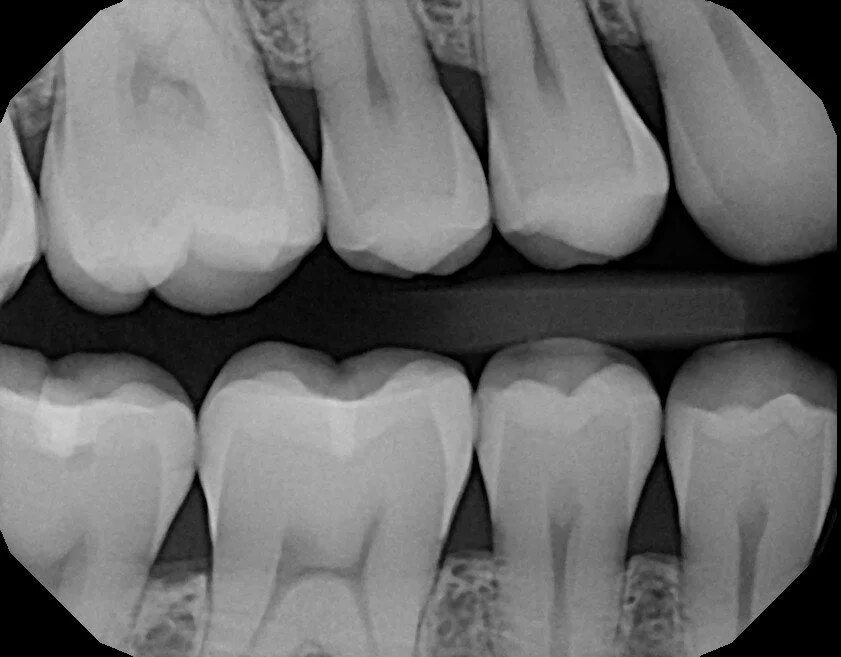

Как понять снимок зуба